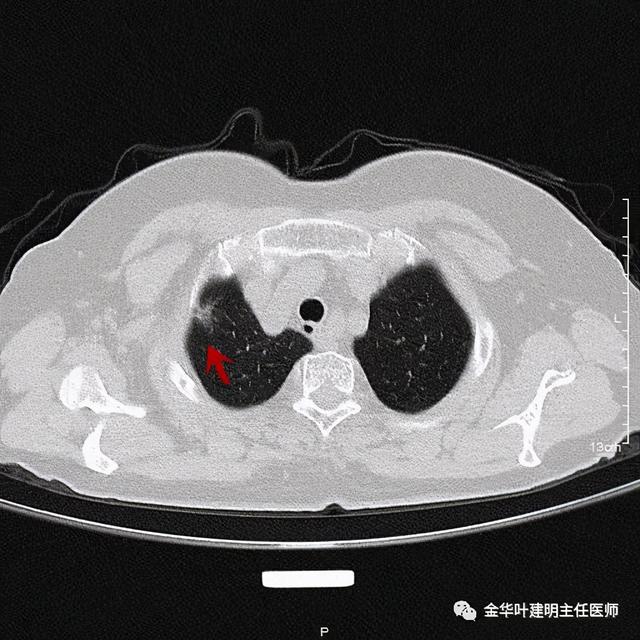

靶扫描更清楚显示瘤肺边界较清、分叶及密度不均杂乱 , 并有少许胸膜牵拉凹陷 , 当然考虑是肺癌 , 而且应该是浸润性腺癌了 。 其长径达2.5厘米!靶扫描还发现了平扫没被注意到的另一个病灶: